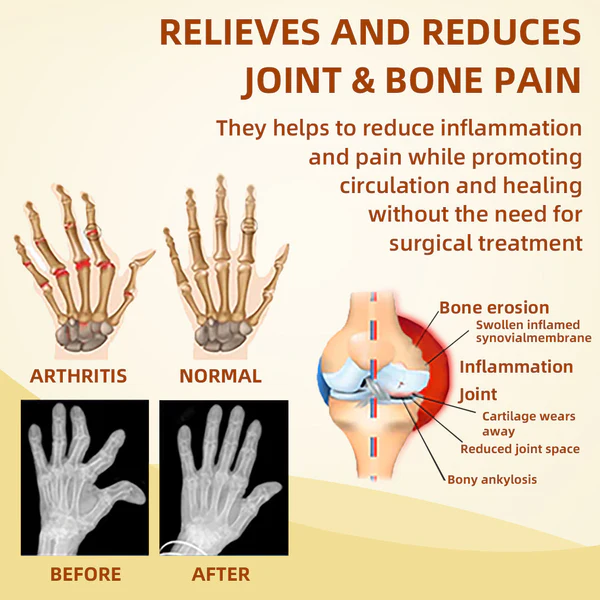

Cvreoz™ Cream effectively treats a wide range of joint problems. including osteoarthritis. rheumatoid arthritis. bursitis. tendonitis. osteoporosis. gout. carpal tunnel syndrome. ligament strains and sprains. thumb deformities. and tennis elbow. among other.

- The kininase and phospholipase A2 in bee venom can promote blood circulation and increase the nutrient supply of joint tissues. thereby promoting the repair and regeneration of joints.

- Melittin in bee venom has a strong anti-inflammatory effect. which can reduce the inflammatory response of arthritis. thereby reducing joint pain and swelling. and improving joint mobility

- Relieve Arthritis Pain

- Eliminate joint inflammation

- Eliminates cysts and edema

- Promotes joint tissue repair

- Improve joint elasticity and mobility

- Promotes joint repair and regeneration

- promote blood circulation